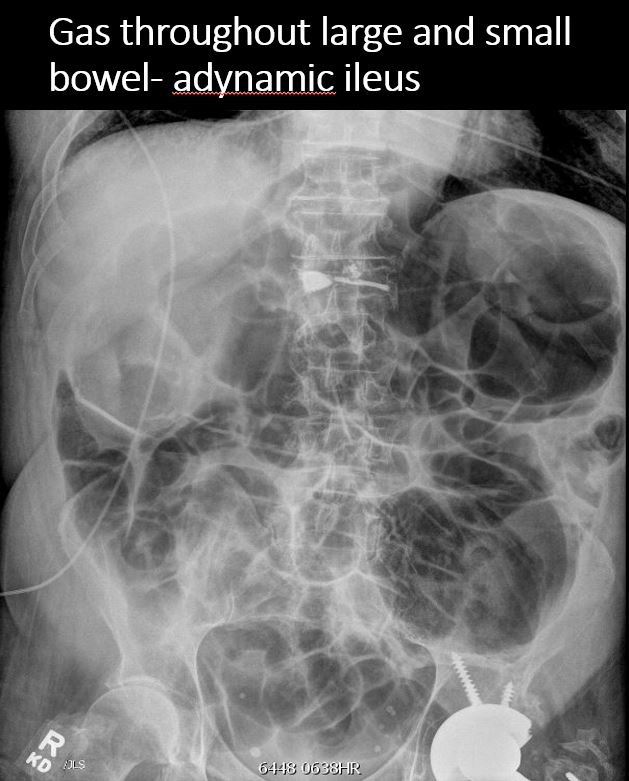

There is scattered extraluminal air or an abnormal focal collection of air in the abdomen or pelvis. |

No | NA |

There is air in the retroperitoneum. |

Yes | NA |

There is retroperitoneal air outlining the right psoas muscle likely from duodenal perforation, from recent endoscopy. There are a few distended loops of small bowel in the mid and lower abdomen.

Notify the clinical team verbally and immediately about retroperitoneal air likely indicating duodenal perforation from recent endoscopy.